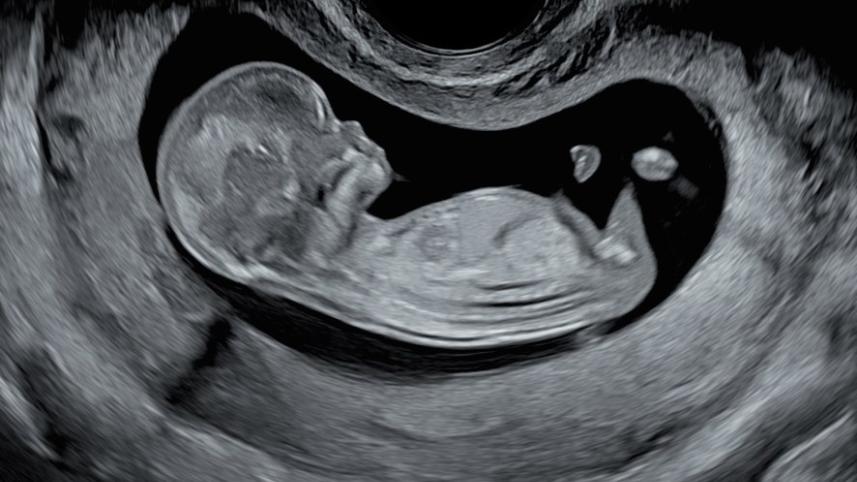

Indian researchers have developed a country-specific model to precisely determine the age of a foetus in a pregnant woman in the second and third trimesters.

The model named Garbhini-GA2 is the first late-trimester GA estimation model to be developed and initially validated using Indian population data. Garbhini-GA2, which uses three routinely measured foetal ultrasound parameters, was developed using GARBH-Ini cohort data documented at Gurugram Civil Hospital, Haryana, and was initially validated in an independent cohort in South India.

Ultrasound dating in early pregnancy is the standard of care for determining GA. However a majority of women in India have their first ultrasound done in their second and third trimester of pregnancy. In these women, the application of Indian population-specific GA formulae, with better accuracy, can potentially improve pregnancy care. This accurate dating will also enhance the precision of epidemiological estimates for pregnancy outcomes in the country.